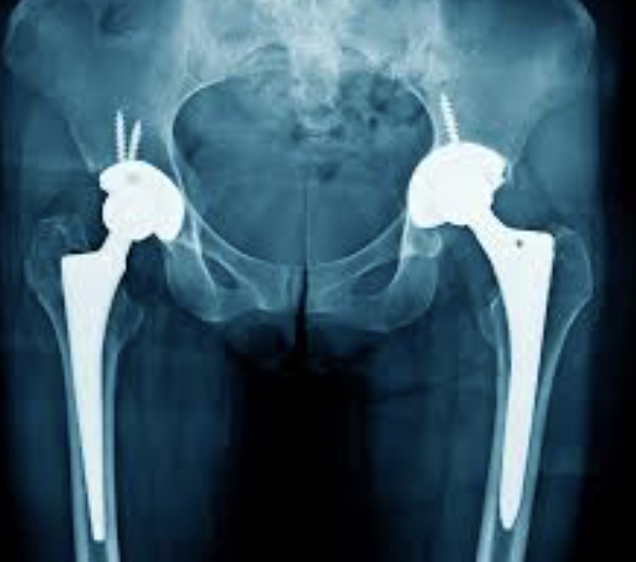

GLUTATION y PROTESIS de CADERA